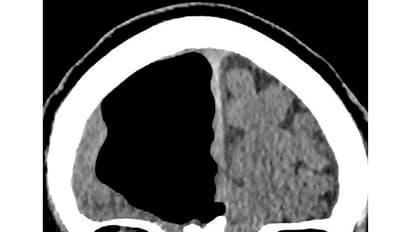

ഇതോടെ സിടി, എംആര്ഐ സ്കാനുകള് ചെയ്യാന് ഡോക്ടര്മാര് ആവശ്യപ്പെട്ടു. സ്കാന് റിപ്പോര്ട്ട് കണ്ടപ്പോള് ഞെട്ടിയത് ഡോക്ടര്മാരായിരുന്നു. അദ്ദേഹത്തിന്റെ തലച്ചോറിന്റെ മുന്നോട്ട് ഉന്തിനില്ക്കുന്ന ഭാഗത്തിന്റെ ഇടതുവശത്ത് ഏകദേശം ഒമ്പത് സെന്റിമീറ്റര് വലിപ്പത്തില് വലിയ ശൂന്യത. തലച്ചോറില്ലാതെ വെറുതെ ഒഴിഞ്ഞു കിടക്കുന്ന ഒരു ഭാഗം. തലയോട്ടിയില് വായു സാന്നിധ്യം കാണുന്ന അവസ്ഥയാണിത്. പുറമെ സൈനസില് ട്യൂമറിന്റെ പ്രാഥമിക ലക്ഷണങ്ങളും കണ്ടെത്തി. സൈനസിലെ ട്യൂമറിന്റെ സാന്നിധ്യം മൂലം അകത്തേക്കെടുക്കുന്ന വായു പുറത്തേക്ക് പോകാത്ത അവസ്ഥയുണ്ടാകുകയും ഇത് തലച്ചോറില് കേന്ദ്രീകരിച്ച് വലിയ മര്ദ്ദമുണ്ടാക്കി തലച്ചോറിനെ ഒരുവശത്തേക്ക് തള്ളി നീക്കിയതാകാമെന്നാണ് ഡോക്ടര്മാരുടെ നിഗമനം.

ബ്രെയിന് സര്ജറി നടത്തുന്നവരിലാണ് ഇത് കാണുന്നതെങ്കിലും ഇതിന് മുമ്പ് ഇത്തരം ശസ്ത്രക്രിയകളൊന്നും ഇദ്ദേഹം നടത്തിയിട്ടില്ല. സാധാരണ വളരെ ചെറിയ എയര്ഹോളുകളാണ് തലയോട്ടിയില് പ്രത്യക്ഷപ്പെടുന്നത്. എന്നാല് ഈ കേസില് മൂന്നര ഇഞ്ച് നീളത്തിലുള്ള എയര് പോക്കറ്റാണ് കണ്ടെത്തിയത്. തലയിലെ ശൂന്യഭാഗത്തെ വായു പുറത്തേക്ക് വിട്ട് മര്ദ്ദം കുറക്കാനുള്ള ശസ്ത്രക്രിയ നടത്താനാണ് ഡോക്ടര്മാര് നിര്ദേശം. എന്നാല് വലിയ അപകട സാധ്യത നിലനില്ക്കുന്ന ശസ്ത്രക്രിയയാതിനാല് ഇതുവരെ ഇക്കാര്യത്തില് അന്തിമ തീരുമാനം എടുത്തിട്ടില്ല.